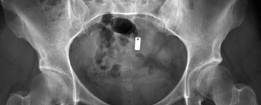

Revision THA Acetabulum Paprosky Type IIIA. ARMD with Metallosis with Severe Periacetabular Osteolysis and Co…

Case Title: Acetabular Impaction Grafting Demographics Age: 78 Sex: female BMI: 28 Relevant Past Medical Hist…